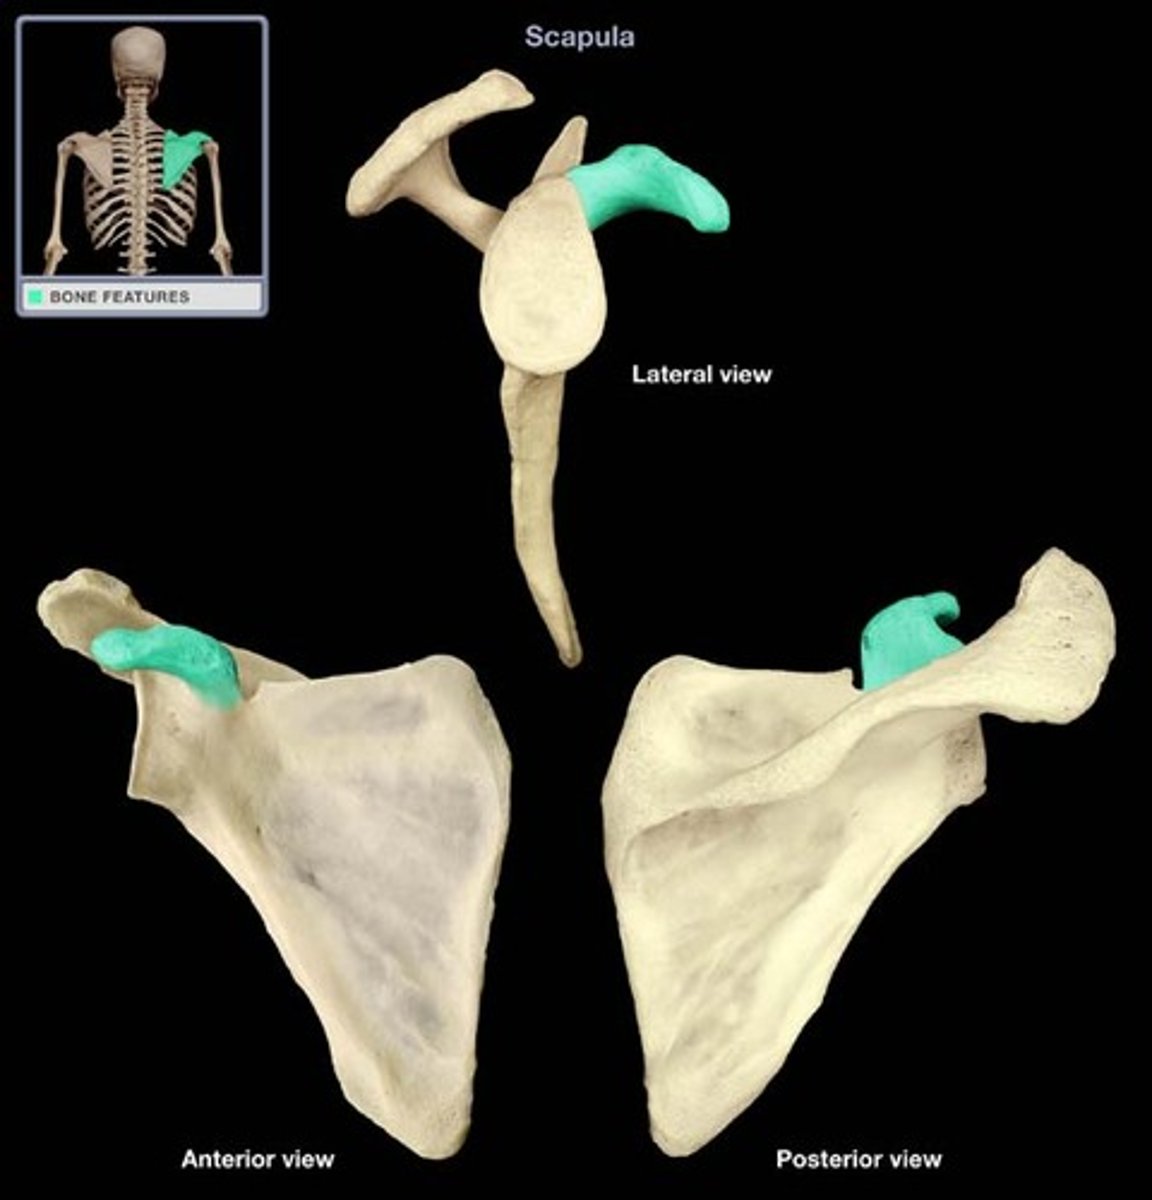

Scapula

shoulder blade

Acromion process

extension of the scapula, which forms the high point of the shoulder

Coracoid process

process above the glenoid cavity that permits muscle attachment

Glenoid fossa

The part of the scapula that joins with the humeral head to form the glenohumeral joint.